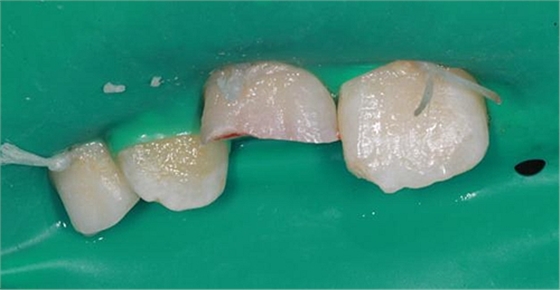

未行麻醉,上橡皮障,給予無(wú)菌鹽水沖洗露髓點(diǎn),可見(jiàn)露髓點(diǎn)滲血,于是給予充分止血,光固化氫氧化鈣蓋髓(voco)(首選MTA蓋髓,但是單位沒(méi)有該材料,只能退而求其次),酸蝕牙釉質(zhì),涂布自酸蝕粘結(jié)劑,斷端碎片給予牙釉質(zhì)全酸蝕,涂布自酸蝕粘結(jié)劑,雙固化樹(shù)脂粘結(jié)固定斷端。最后給予初步拋光?;純杭议L(zhǎng)表示滿意。

術(shù)后A1粘結(jié)斷端處可見(jiàn)接縫,建議患兒擇日進(jìn)行樹(shù)脂修復(fù),同時(shí)恢復(fù)B1切角。因此患兒情況特殊,根尖未閉合,無(wú)法進(jìn)行去髓,故牙髓存在壞死感染可能,醫(yī)囑定期復(fù)查,如有情況及時(shí)處理。